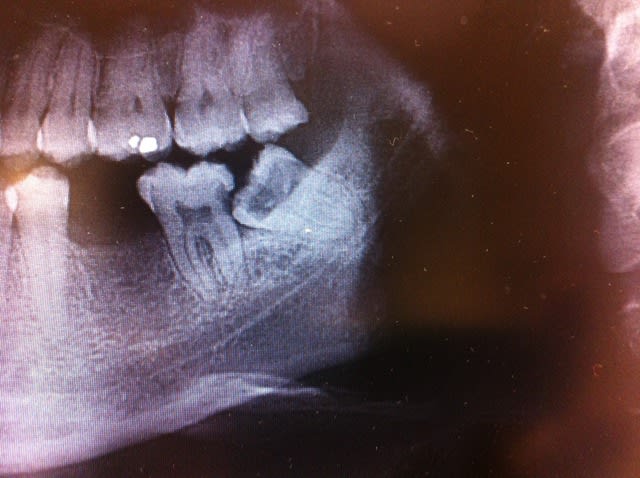

Voici le scanner d'un patient chez qui l'extraction des dents 47 et 48 est indiquée. Etant donné le positionnement de ces dents par rapport au nerf, j'aurais aimé avoir vos différents points de vue quant à la meilleure solution thérapeutique à adopter.

Pour la 47 il faut éviter les mouvements d'élévation intempestif qui entraînerait une compression de la racine sur le nerf, même si ça n'entraînera pas de PB permanent (une repousse axonale se fera en travers de la gaine de myéline)

48 séparation radic, pas de coronectomie

Peu de risque de paresthésie définitive ici

Je te conseillerais de commencer par sectionner la 48 comme je l'ai tracé sur l'image jointe.

La 48 semble s'emboîter dans la carie distale de 47 et risque de la bloquer. Ensuite je tenterais de les mobiliser avant de décider la séparation des racines.